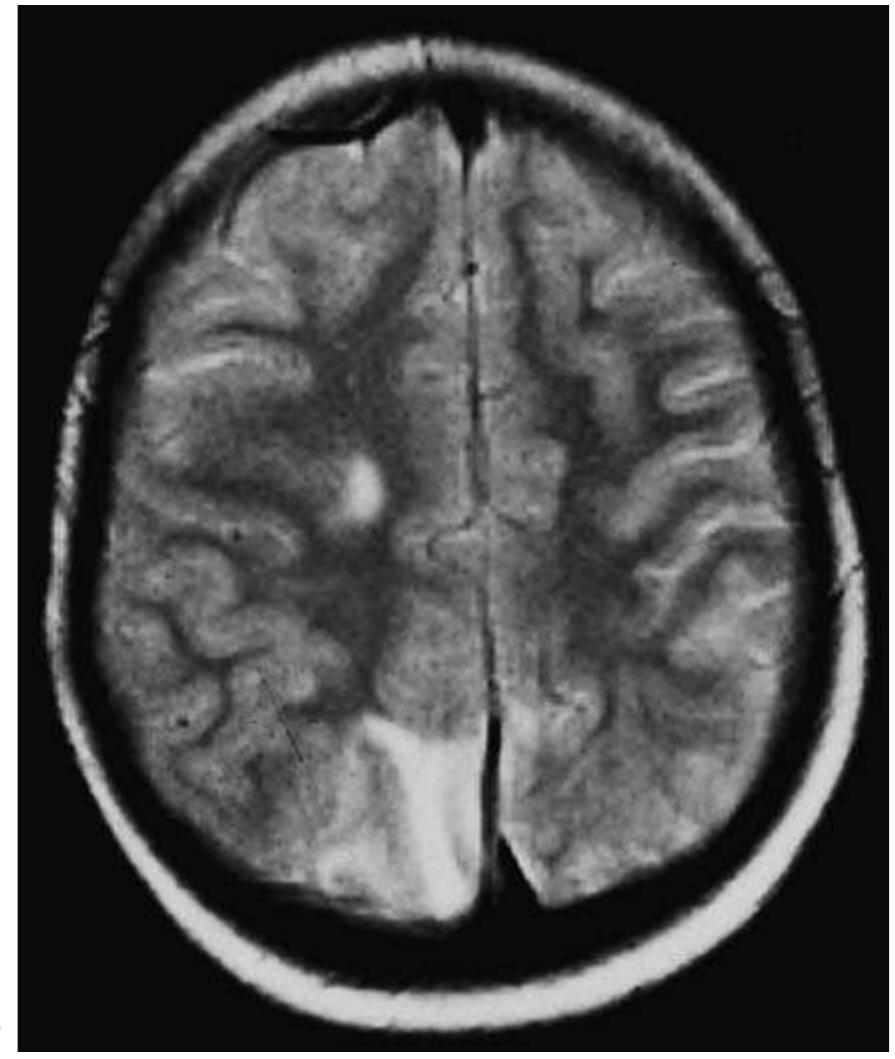

![Fig. 4.1 - Extrapontine myelinolysis in an alcoholic patient. The MRI demonstrates multiple areas of hyperintensity within the hemispheric subcortical hemispheric white matter, the deep hemispheric white matter and the midbrain. [a) coronal FLAIR MRI; b, c, d) axial T2-weighted MRI].](https://figures.academia-assets.com/35610716/figure_255.jpg)